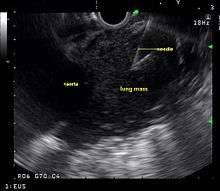

Endoscopic ultrasound (EUS) is an endoscopic technique where a miniaturized ultrasound probe is passed though the mouth into the upper gastrointestinal tract to investigate organs and structures close to the esophagus, stomach, or duodenum, such as the lung. In 1993, Wiersema published the first description of EUS to diagnose and stage lung cancer,[27] done by advancing a fine needle through the esophagus into adjacent lymph nodes. Numerous subsequent studies have shown this general methodology to be effective, very safe, minimally invasive, and very well tolerated. Given these advantages, many authorities think that EUS together with endobronchial ultrasound (EBUS) enhances lung cancer diagnosis and staging.[28]

Endoscopic ultrasound (EUS)

A metaanalysis published in 2007, based on 1,201 cancers in 18 high-quality clinical trials carefully selected by predefined criteria from the literature, systematically examined the performance of EUS-guided FNA in NSCLC staging. Two scenarios were considered: the setting of enlarged lymph nodes on CT (suggestive but not diagnostic of cancer), and the obverse scenario of an absence of lymph node enlargement on CT (suggestive but not diagnostic of no cancer).[24] Overall, in both settings, minor complications were reported in 0.8% of procedures; no major complications were recorded. EUS-FNA in enlarged discrete mediastinal lymph nodes had an excellent pooled sensitivity (8 studies) of 90% (95% CI, 84 to 94%) and specificity of 97% (95% CI, 95 to 98%). EUS-FNA in the setting of no enlarged mediastinal lymph nodes on CT had a pooled sensitivity (4 studies) of 58% (95% CI, 39 to 75%) and specificity of 98% (95% CI, 96 to 99%). Although this sensitivity (58% in CT-negative disease) might on first consideration seem disappointing, if EUS is performed as a staging test it can help avoid more invasive staging procedures, or surgery, if positive (for the presence of cancer). In other words, an EUS that has a positive result (shows cancer) will avoid further needless surgery, whereas a result not showing cancer may be false-negative, and probably requires an excisional biopsy technique for confirmation, such as VATS or mediastinoscopy.

EUS can reliably reach the lymph node stations 5, 7, 8 and 9. In the superior mediastinum the trachea is somewhat to the right of the esophagus which makes it often possible to reach left-sided area 2 and 4 lymph nodes and, less often, right sided paratracheal lymph nodes.[29] In general, EUS is most appropriate for evaluation of the posterior inferior mediastinum while mediastinoscopy or EBUS are best for the anterior superior mediastinum. The feasibility of EUS-FNA of aorto-pulmonary window (subaortic) lymph nodes (station 5) is a major advantage of EUS. Evaluation of this station has traditionally required a paramedian mediastinotomy (Chamberlain procedure). EUS can easily sample celiac lymph nodes, which cannot be reached by the other mediastinal staging methods. In one recent study an unexpectedly high incidence of celiac lymph node metastasis (11%) was noted.[30] EUS can also be used to biopsy potential left adrenal metastases, whereas the right adrenal gland is mostly inaccessible.[31]